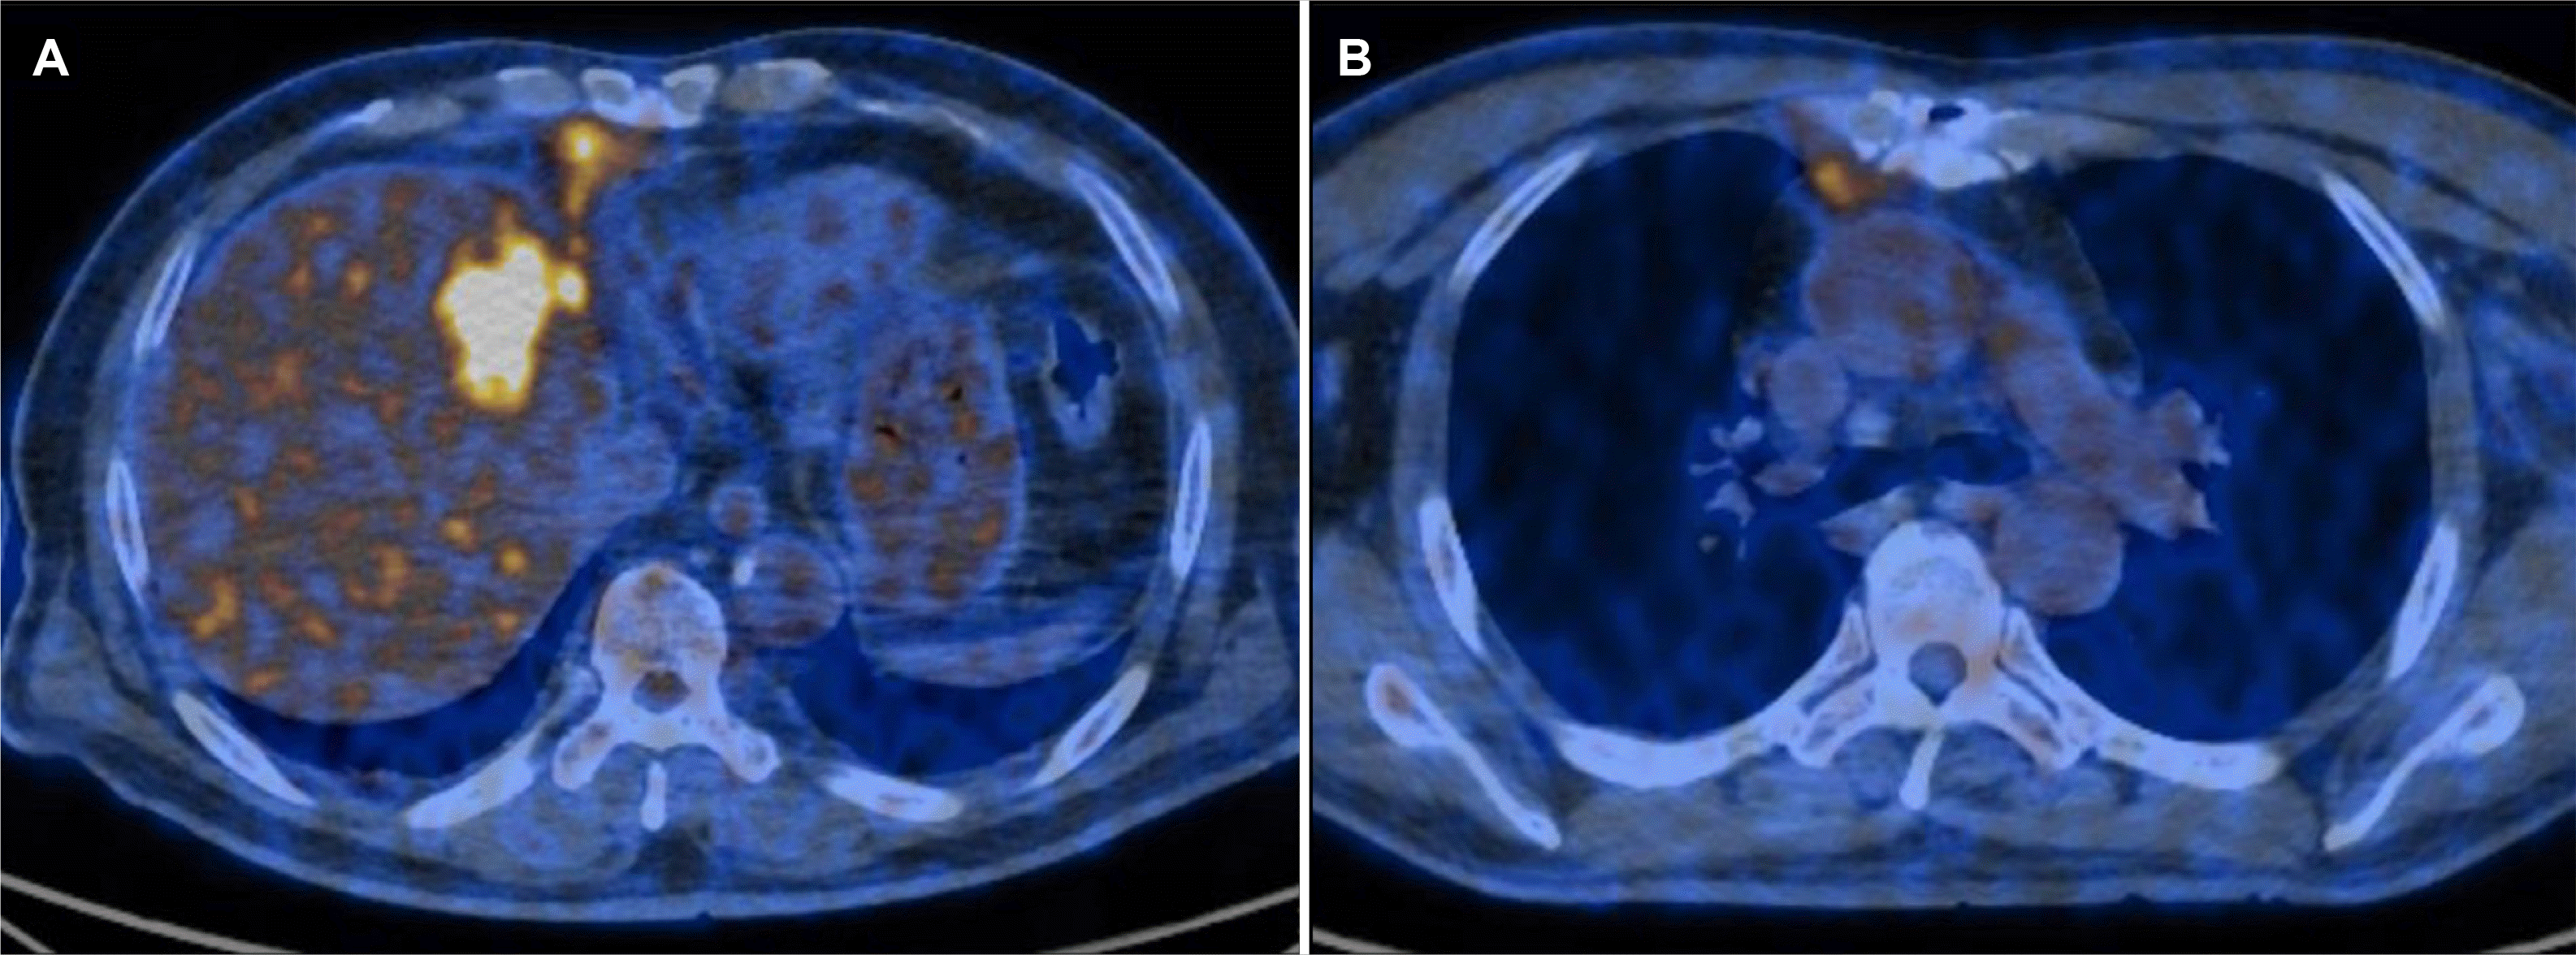

Fig. 6

(A) PET CT scan showing a hypermetabolic mass involving the segment 4 area of the liver. (B) Hypermetabolic lesions in the right internal mammary region. PET CT, positron emission tomography-computed tomography.

Initially, empirical antibiotic treatment with moxifloxacin was started, and percutaneous catheter drainage (PCD) was performed to manage the suspected liver abscess. The drainage fluid was yellowish and turbid, with the analysis showing a white blood cell count exceeding 100,000 cells/mm³ with 97% polymorphonuclear neutrophils, a protein level of 1,490 mg/dL, an albumin concentration of 940 mg/dL, and a CEA level of 10,600 ng/mL. The cytology of the fluid revealed a few atypical cells, but subsequent evaluations were negative for malignant cells (Fig. 4). The entamoeba histolytica IgG serology was negative. No growth was observed in cultures. A liver biopsy performed six days after sufficient drainage revealed a moderately differentiated adenocarcinoma with tumor necrosis, leading to the final diagnosis of primary cholangiocarcinoma (Fig. 5). Positron emission tomography-computed tomography revealed hypermetabolic lesions in segment 4 and the right internal mammary nodal chain (Fig. 6). A biliary CT was performed 22 days after inserting the PCD, which showed that the abscess had collapsed compared to previous imaging. On the other hand, the lesion suspected to be cholangiocarcinoma showed no significant change (Fig. 7). The PCD output remained consistently brown-yellowish, with daily volumes ranging from 100 to 150 cc since its insertion, and never decreased below 50 cc. The drainage characteristics were not thick or pus-like, and the output remained stable despite being drained for more than 21 days, which reduced the likelihood of a liver abscess. Consequently, the catheter was maintained in situ. Nevertheless, the drainage volume remained above a certain level, so the patient continued the drainage while initiating systemic chemotherapy.